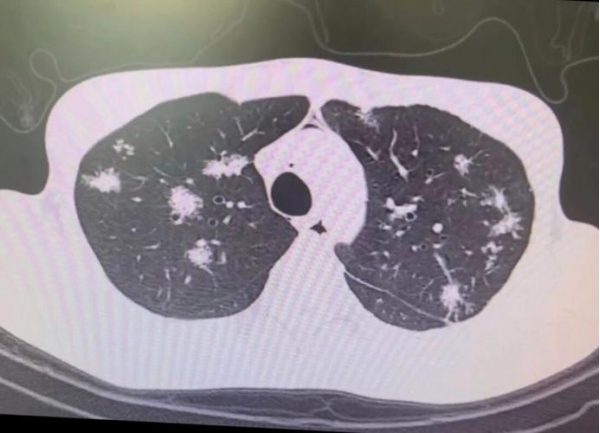

3、CT复查 + 舌象对照:影像看"形",舌象看"气",两者结合,更懂结节背后的故事。